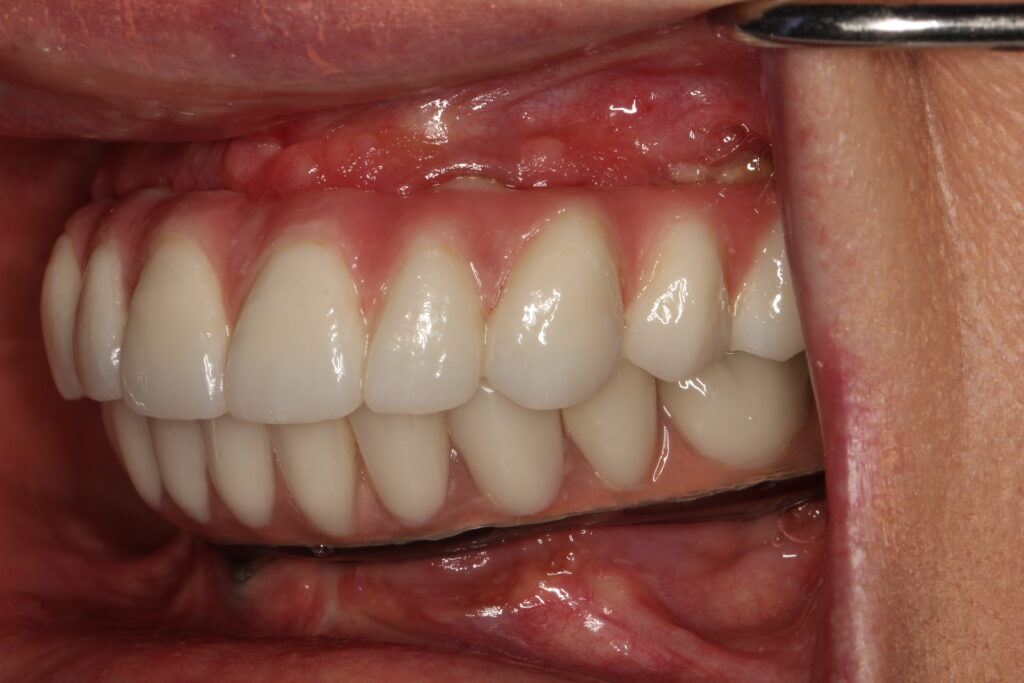

A selection of full arch fixed implant bridge patients after 5 years of wear